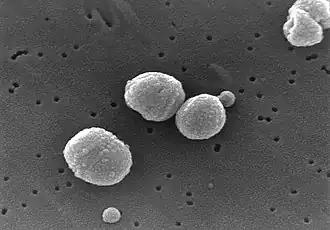

Streptococcus pneumoniae — частый возбудитель бактериальной пневмонии | |

Пневмони́я (др.-греч. πνευμονία — «болезнь лёгких», от др.-греч. πνεύμων — «лёгкое»[2]), воспаление лёгких — воспаление лёгочной ткани обычно инфекционного происхождения с преимущественным поражением альвеол (развитием в них воспалительной экссудации)[3][4]. Пневмонии, вызванные инфекциями, являются формой острой респираторной инфекции, затрагивающей лёгкие[5]. Основными возбудителями пневмонии являются бактерии и вирусы, реже её вызывают микоплазмы, грибы и паразиты[6].

«Типичная» пневмония характеризуется резким подъёмом температуры, кашлем с обильным выделением гнойной мокроты и, в некоторых случаях, плевральной боли. При исследовании: укорочение перкуторного звука, жёсткое дыхание, усиленная бронхофония, усиленное голосовое дрожание, сначала сухие, а затем влажные, крепитирующие хрипы, затемнение на рентгенограмме. Такую пневмонию вызывают Streptococcus pneumoniae, Haemophilus influenzae, Escherichia coli, Klebsiella pneumoniae.

Возбудителем крупозной пневмонии (плевропневмонии) является пневмококк. Пневмония, вызванная этим микробом, отличается своей масштабностью и тяжестью течения. Начало крупозной пневмонии острое. Температура тела повышается до 39—40 °C. Одышка наблюдается с первых дней болезни. Для этого вида пневмонии характерны поражения одной доли лёгкого, целого лёгкого или обоих лёгких. Чем больше объём поражения лёгких, тем тяжелее протекает процесс. На 3-4 день болезни появляются характерная ржавая мокрота и кашель. При кашле больной жалуется на сильные «колющие» боли в груди со стороны лёгкого, захваченного пневмонией. При очаговой пневмонии боли в груди, напротив, наблюдаются очень редко. При объективном обследовании первая стадия характеризуется сохранением везикулярного дыхания и притупленно-тимпаническим перкуторным звуком. Также выслушивается дополнительный дыхательный шум — крепитация — crepitatio indux. Во второй стадии — дыхание бронхиальное и тупой перкуторный звук. Подвижность нижнего лёгочного края поражённой стороны снижена. В третьей стадии как и в первой — везикулярное дыхание и притупленно-тимпанический перкуторный звук, а также крепитация — crepitatio redux.

Впервые пневмония была описана Гиппократом примерно в 460 году до нашей эры, однако вплоть до XIX века не было известно, что она является именно инфекцией лёгких, а не симптомом других заболеваний[39]. Первые клинические и патологические проявления были описаны французским врачом Рене Лаэннеком в 1819 году, а в 1842 году австрийский патолог Карл Рокитанский первым дифференцировал пневмонию на долевую и бронхопневмонию[40]. Инфекционная природа была обнаружена в 1875 году немецким патологом Эдвином Клебсом, который под микроскопом наблюдал бактерии, а в 1884 году Карл Фридлендер и Френкель, Альберт смогли определить два наиболее распространённых возбудителя пневмонии на то время — Streptococcus pneumoniae (пневмококк) и Klebsiella pneumonia[39].